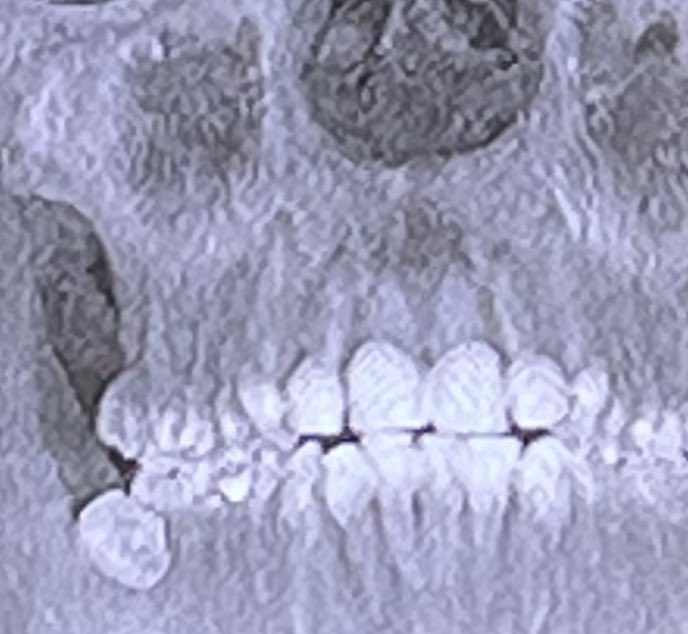

#Splatoon3 LIKES AND RETWEETS APPRECIATED: Let me clear things up, according to both my dentist and surgeon I will die if these are not taken out within a month. Insurance will not cover the surgery, so that’s why I’m tryna push to raise money on stream. 1/3